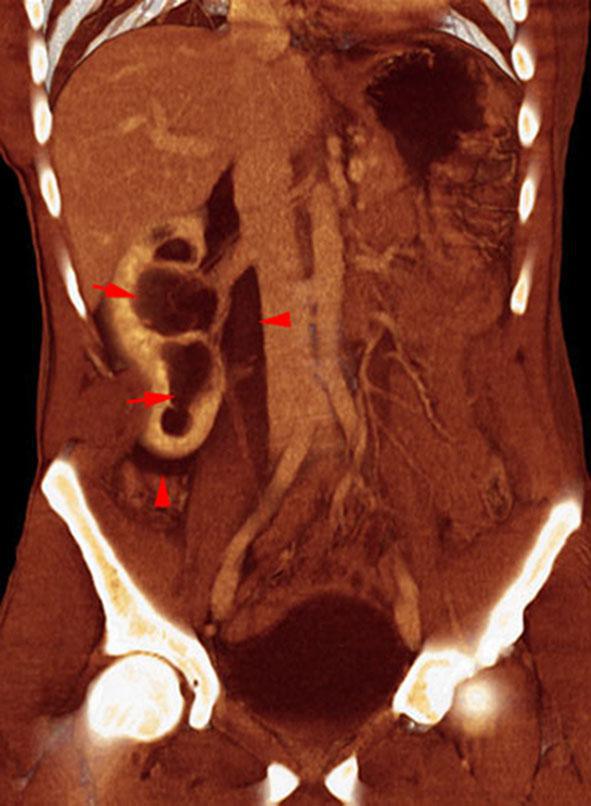

Estallido renal